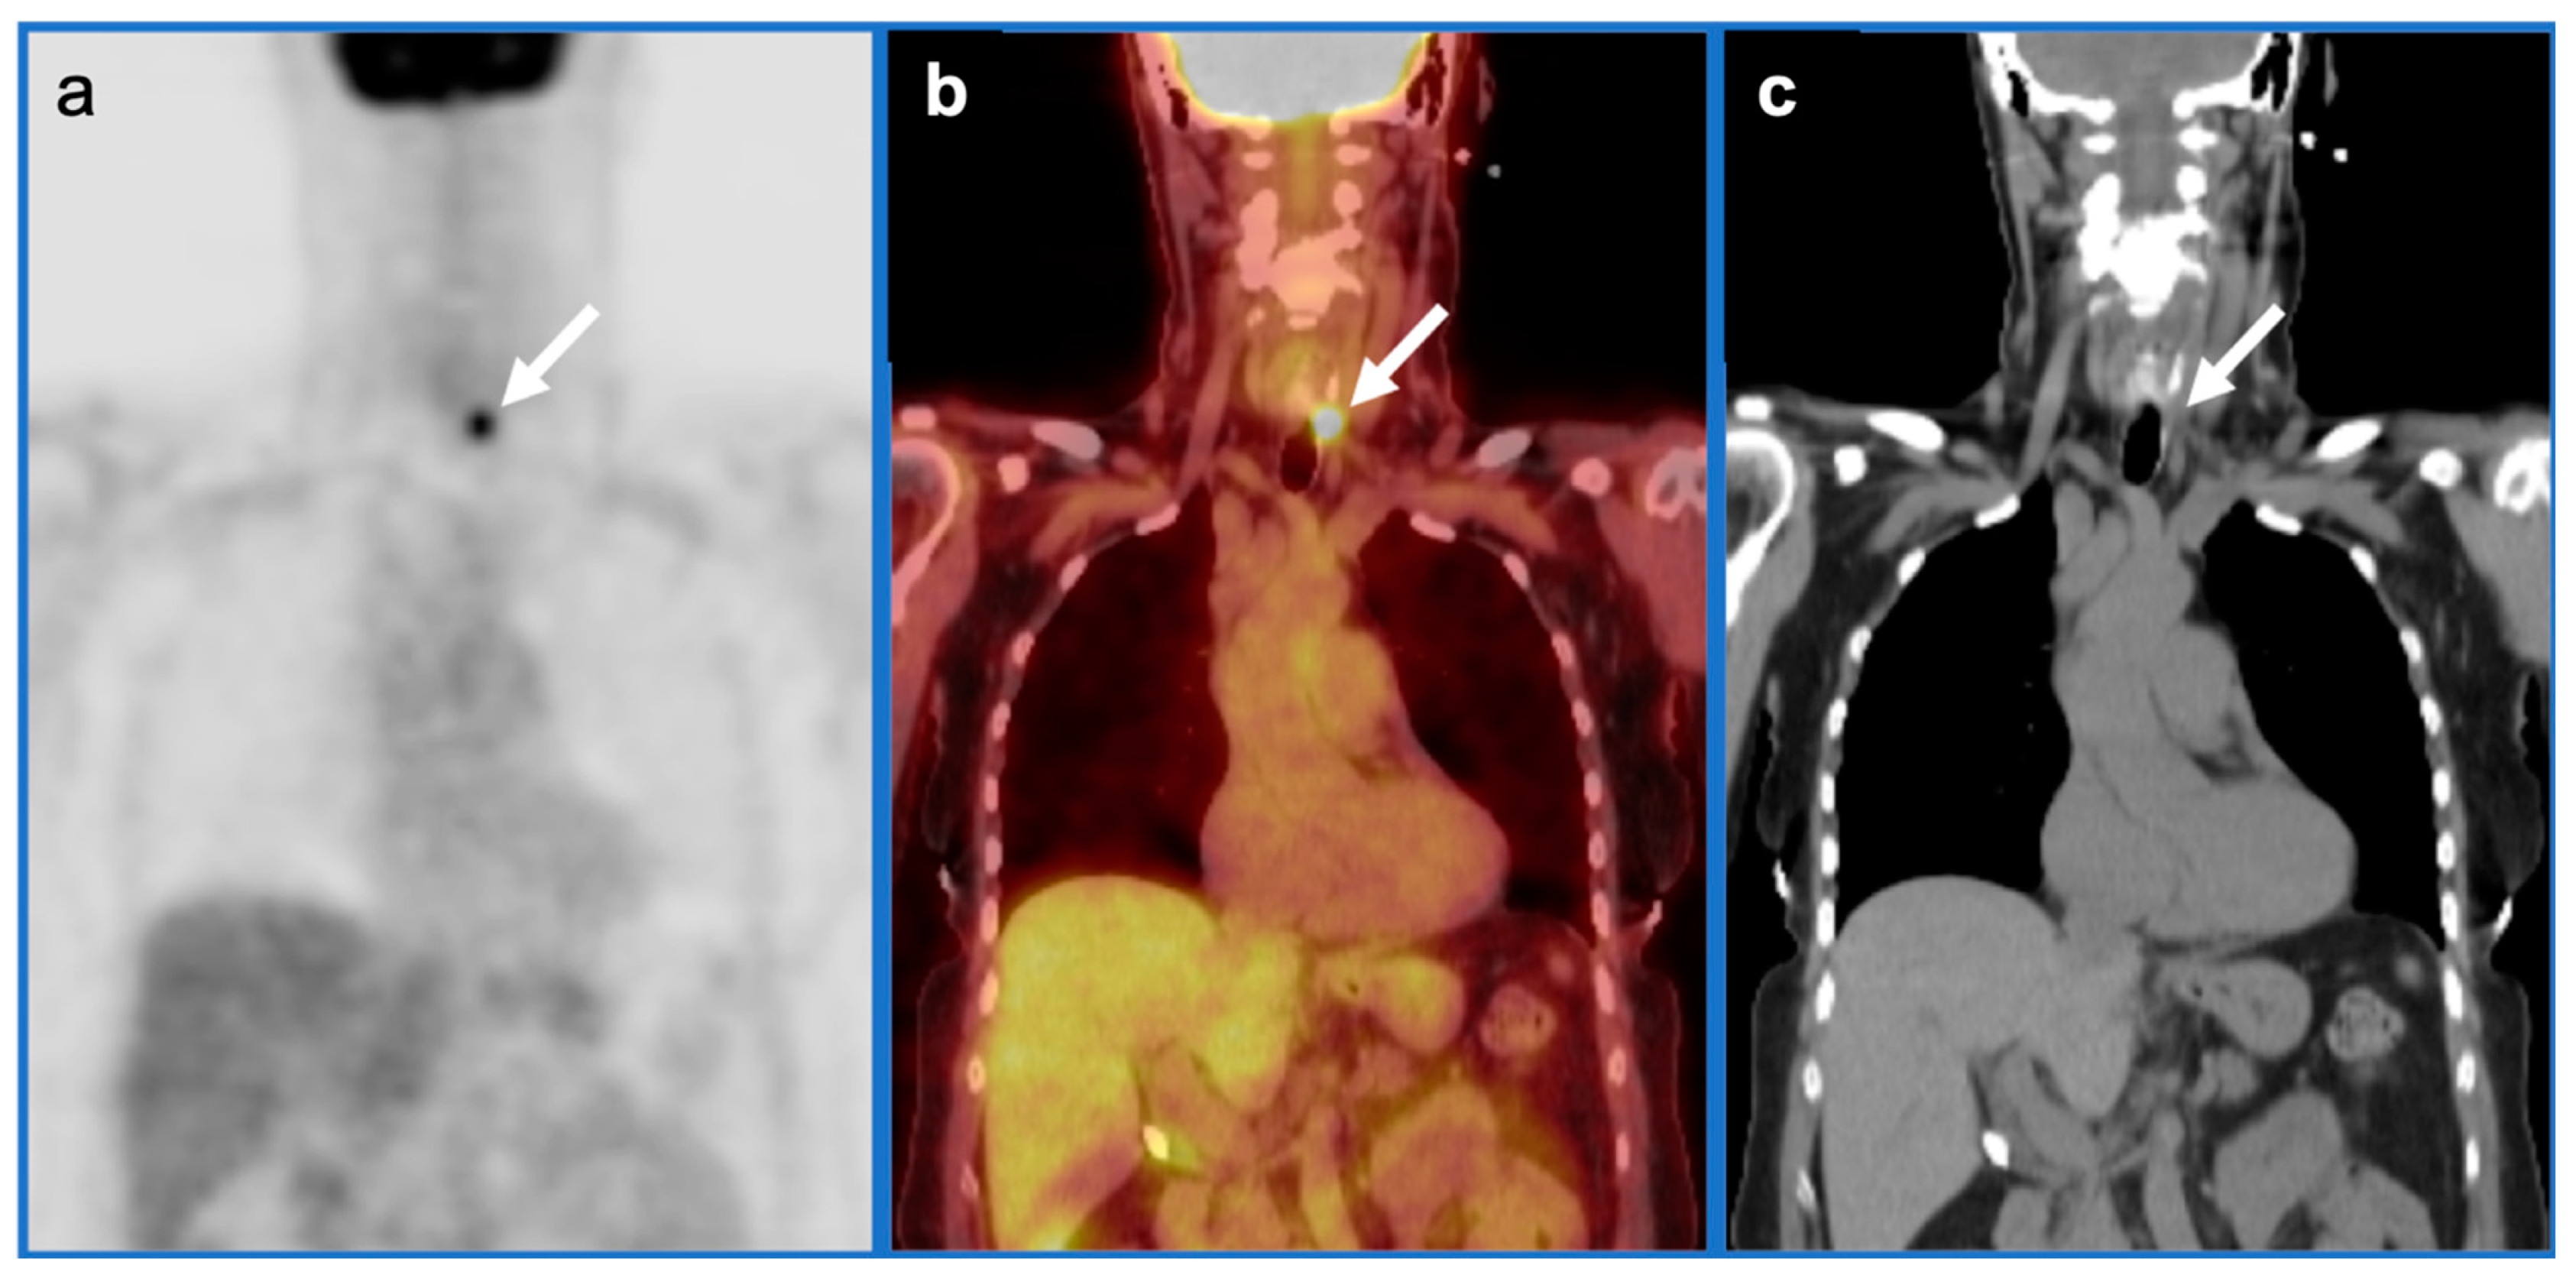

2.6. Thyroid Cancer

- Medullary thyroid cancer